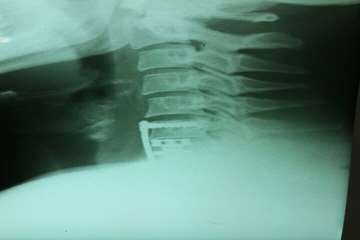

در این عمل جراحی پیچیده و 4ساعته از گردن به ستون فقرات اپروچ شد و جسم مهره C7گردنی با کمک فرز وبا استفاده از میکروسکوپ به طور کامل تراشیده شد و فشار از روی نخاع گردنی برداشته شد.(کورپکتومی)

سپس برای حفظ پایداری ستون فقرات،بجای جسم مهره C7از مش کیج EXPANDABLE از جنس تیتانیوم استفاده شد.در نهایت یک PLATE بر روی مهره آسیب دیده قرار داده شده و با کمک 4 پیچ روی مهره بالا (C6) و مهره پایین (T1) فیکس شد.